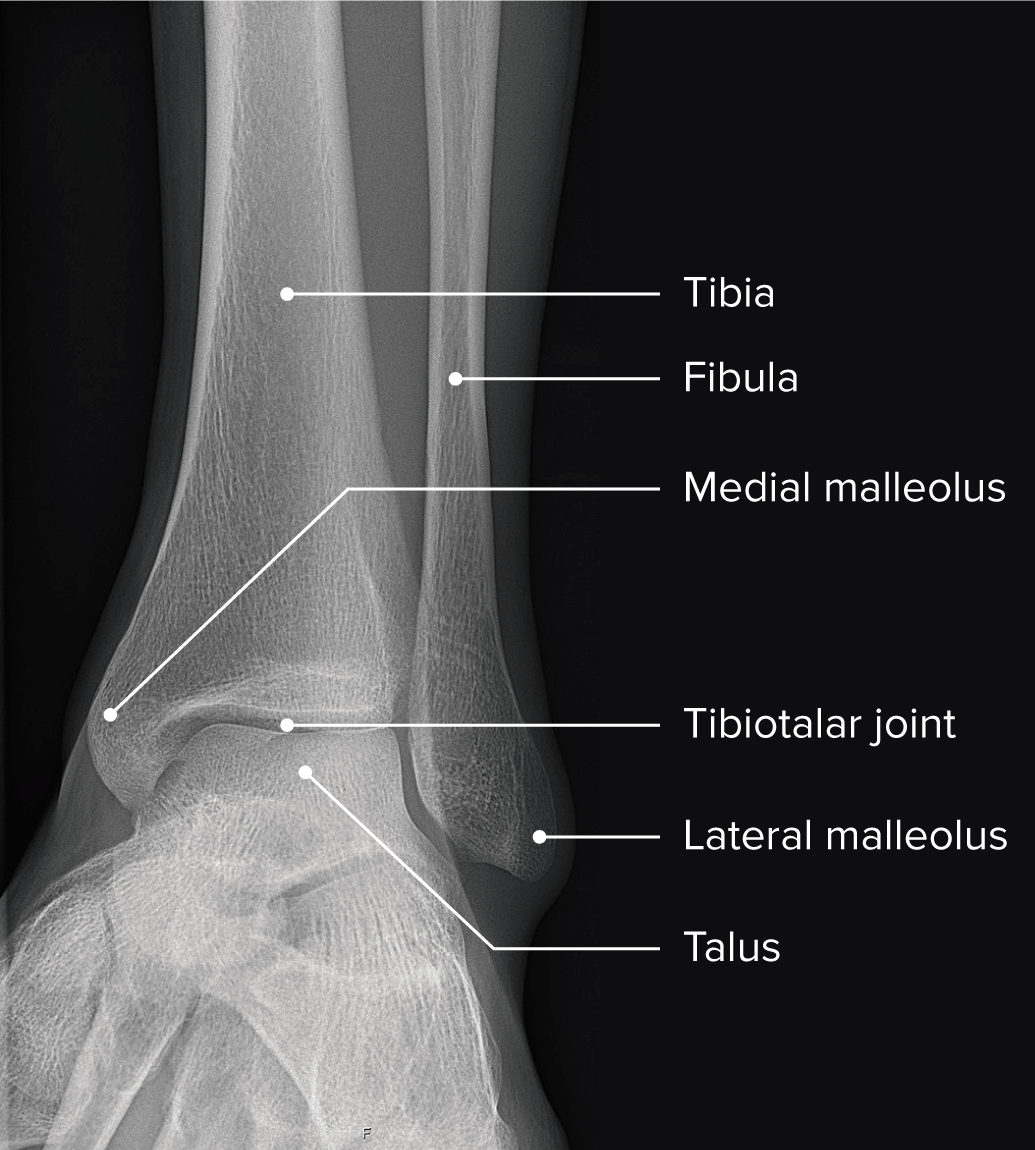

Articulación del Tobillo Anatomía Concise Medical Knowledge Cajon Anterior Del Tobillo La inestabilidad después de los esguinces de tobillo, particularmente los esguinces laterales, se evalúa mediante la prueba del cajón anterior. Las principales pruebas para el tobillo lateral son: La prueba del cajón anterior evalúa esencialmente el ligamento astragaloperoneo anterior y debe realizarse en ligera flexión. La prueba del cajón anterior del tobillo se realiza para evaluar la estabilidad del ligamento. Cajon Anterior Del Tobillo.